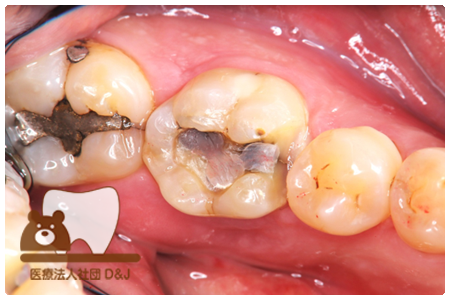

症例8フルジルコニアクラウン

治療前

治療中

治療後

29歳 女性

- 治療内容

- 銀歯からフルジルコニアクラウンへの修復

- 治療期間

- 根の治療含め3か月

- 費用

- 自費

フルジルコニアクラウン:77,000円(税込)

- その他の治療の費用は含まれておりません。

- リスク・副作用

- 強い衝撃が加わると欠けたり割れたりする可能性があります。また、噛み合わせの状態によっては脱離や周囲の歯への影響が出ることもあります。